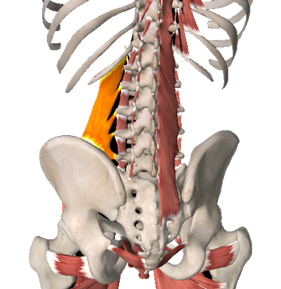

Als je schrikt, duik je automatisch in elkaar: je trekt je schouders op, je rug kromt zich als een soort schild. Een belangrijke beschermende spiergroep hierbij zijn de psoasspieren. Samen vormen deze spieren een systeem dat de romp, het bekken en de benen verbindt. De meeste sympathische zenuwen, waaronder de vecht- en vluchtzenuwen, bevinden zich in dit gebied. De psoasspieren ondersteunen de vecht- vluchtreactie van het menselijk organisme. Deze spieren zijn een soort van wachtposten in het centrum van het lichaam. Ze verbinden de rug met het bekken en de benen. Bij gevaar trekken de psoasspieren samen.

Samentrekkende psoasspieren laten het lichaam vooroverbuigen. Gespannen of beschadigde psoasspieren kunnen hevige pijn in de onderrug veroorzaken. Dit komt bijvoorbeeld veel voor bij mensen die seksueel misbruikt zijn. Secundaire rugpijn of beenpijn ontstaat hier veelal bij, doordat het lichaam probeert de voorwaartse trek van het lichaam te compenseren. De lange rechte rugspieren trekken het lichaam naar achter in een poging het staande te houden. Hierdoor ontstaat er spanning op de ruggenwervel, wat op den duur chronische schouder- en nekklachten tot gevolg kan hebben. Daarnaast kan de middenrifspier ook spanning in dit gebied veroorzaken.

Om te herstellen van fysieke traumatische spanningen moeten vooral de diepliggende psoasspiergroep, de spieren waarmee je de rug strekt (de erector spinae) en de schouder- en nekspieren hun defensieve spanning weer loslaten en terugkeren in de ontspannen toestand.

5. Vierhoekige lendenspier

6. Grote lendenspier en darmbeenspier